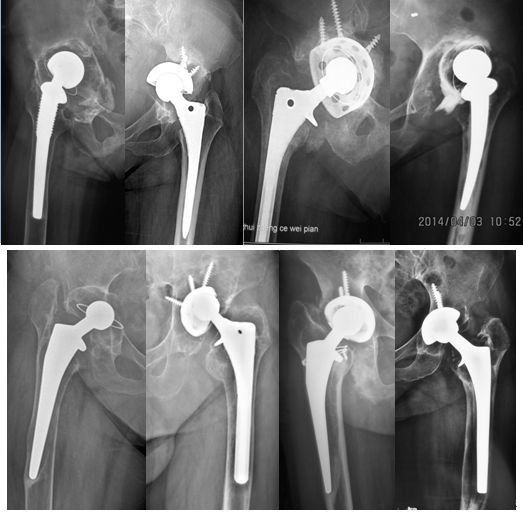

图1 各种原因所致人工髋关节翻修

人工髋关节翻修术最常见的原因有假体松动、感染、脱位、假体周围骨折等。一般而言,人工髋关节翻修后,假体的使用寿命比初次置换要短一些,主要原因是患者的骨组织质量不如初次置换时坚韧。对于已经明确松动、感染、反复脱位的患者,不要长时间拖延,而应该及时翻修,从而降低手术难度,提高翻修的成功率。